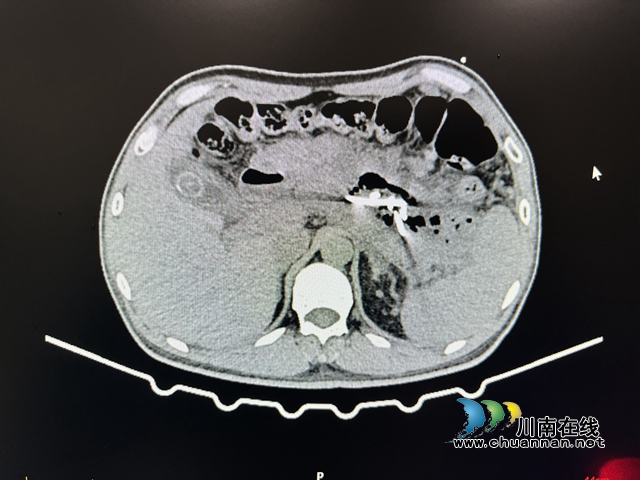

检查发现,原有的胰腺假性囊肿体积已经扩大到14.5×20.4cm,由于体积巨大,已经压迫到了周围组织器官,需要立即手术切除。

治疗前

术后,李先生腹痛、腹胀的症状很快缓解,术后一周复查CT,囊肿已基本消退,现已出院。